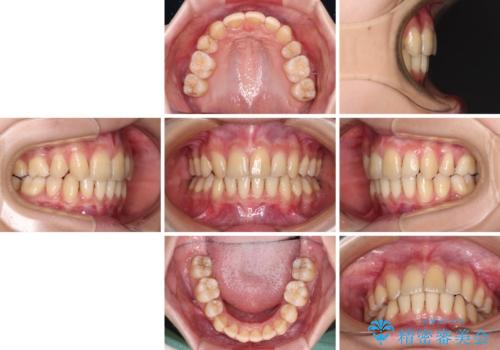

出っ歯を治したい ワイヤー装置による抜歯矯正

- 上下の出っ歯を気にして来院された患者様です。

口元を積極的に引っ込めるために、上下左右の小臼歯を4本抜歯することとしました。

右上前から2番目の歯が欠損しているため、①矯正治療により欠損部にスペースを作りインプラント補綴を行って前歯を左右対称に揃える、②左右非対称となるが、欠損補綴を行わずに排列する、のいずれかとなりますが、患者様と相談の上②にて矯正治療を行うこととしました。

変則的な歯列であったため、奥歯がしっかりと咬み合うのか、前歯はしっかりと排列できるのかと不安ではありましたが、結果としてはきれいに整った歯列にて終了することができました。